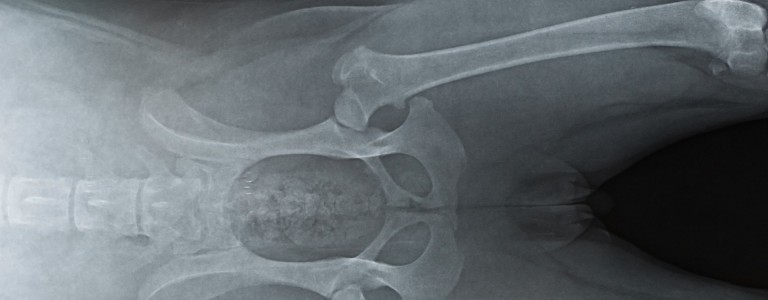

Vice rédhibitoire chien dysplasie coxo fémorale

Cette atteinte correspond à une malformation progressive de la hanche pouvant se manifester à n'importe quel stade de vie.

En général on remarque la dysplasie plutôt chez le chien adulte.

Les symptômes peuvent être une démarche ondulante, un déplacement des membres postérieurs en simultanée jusqu'à une raideur avec ou sans boiterie.

Cette maladie peut exister chez la majorité des races mais est surtout fréquente chez les plus grands gabarits.

La dysplasie favorise l'apparition d'arthrose.

Cette pathologie est principalement congénitale mais peut également être causée par des facteurs externes durant la croissance.

Un excès d'exercice, des mauvaises sollicitations, un excès pondéral et une alimentation non adaptée au chiot peuvent provoquer une dysplasie.

En fonction du stade de la dysplasie et si celle-ci est bien suivie, l'animal peut tout de même avoir une qualité de vie décente.

Il existe un dépistage précoce afin de limiter la dégénérescence (régime alimentaire, activité physique, traitement médical ou chirurgical).

A l'adoption d'un chien de grande taille, il est conseillé d'effectuer une radio des hanches avant 1 an même sans signe clinique afin d'être en mesure d'effectuer une action en rédhibition ou de consulter le vendeur.

Seuls les clichés médicaux pris avant les un an de l'animal peuvent être pris en considération.